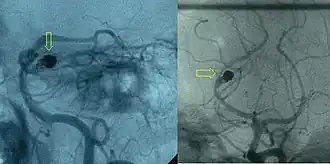

Angiography

After a subarachnoid hemorrhage is confirmed, its origin needs to be determined. If the bleeding is likely to have originated from an aneurysm (as determined by the CT scan appearance), the choice is between cerebral angiography (injecting radiocontrast through a catheter to the brain arteries) and CT angiography (visualizing blood vessels with radiocontrast on a CT scan) to identify aneurysms. Catheter angiography also offers the possibility of coiling an aneurysm (see below).[4][30]

If a cerebral aneurysm is identified on angiography, two measures are available to reduce the risk of further bleeding from the same aneurysm: clipping[56] and coiling.[57] Clipping requires a craniotomy (opening of the skull) to locate the aneurysm, followed by the placement of clips around the neck of the aneurysm. Coiling is performed through the large blood vessels (endovascularly): a catheter is inserted into the femoral artery in the groin and advanced through the aorta to the arteries (both carotid arteries and both vertebral arteries) that supply the brain. When the aneurysm has been located, platinum coils are deployed that cause a blood clot to form in the aneurysm, obliterating it. The decision as to which treatment is undertaken is typically made by a multidisciplinary team consisting of a neurosurgeon, neuroradiologist, and often other health professionals.[4]

In general, the decision between clipping and coiling is made on the basis of the location of the aneurysm, its size and the condition of the person. Aneurysms of the middle cerebral artery and its related vessels are hard to reach with angiography and tend to be amenable to clipping. Those of the basilar artery and posterior cerebral artery are hard to reach surgically and are more accessible for endovascular management.[58] These approaches are based on general experience, and the only randomized controlled trial directly comparing the different modalities was performed in relatively well people with small (less than 10 mm) aneurysms of the anterior cerebral artery and anterior communicating artery (together the "anterior circulation"), who constitute about 20 percent of all people with aneurysmal SAH.[58][59] This trial, the International Subarachnoid Aneurysm Trial (ISAT), showed that in this group the likelihood of death or being dependent on others for activities of daily living was reduced (7.4 percent absolute risk reduction, 23.5 percent relative risk reduction) if endovascular coiling was used as opposed to surgery.[58] The main drawback of coiling is the possibility that the aneurysm will recur; this risk is extremely small in the surgical approach. In ISAT, 8.3 percent needed further treatment in the longer term. Hence, people who have undergone coiling are typically followed up for many years afterwards with angiography or other measures to ensure recurrence of aneurysms is identified early.[60] Other trials have also found a higher rate of recurrence necessitating further treatments.[61][62]